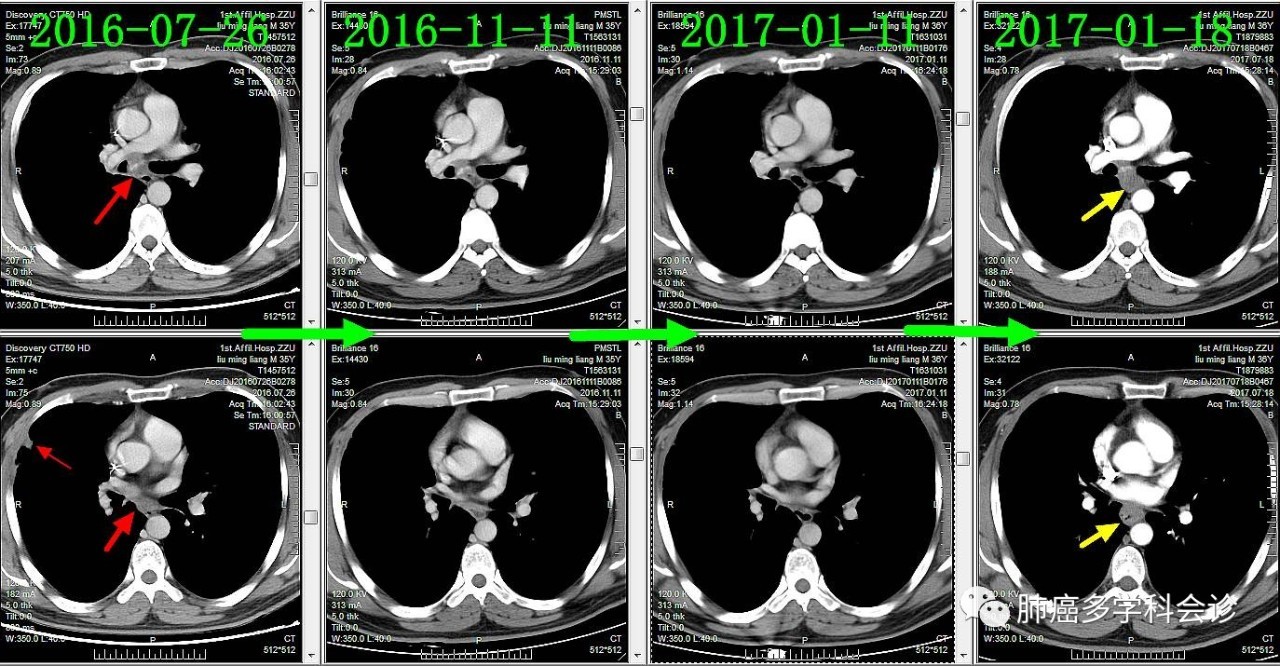

下面通过对比治疗过程中胸部CT变化,展示胸部肿瘤此消彼长的过程:

肺原发灶略有缩小

纵隔肿大淋巴结逐渐缩小

胸膜转移灶消失

-